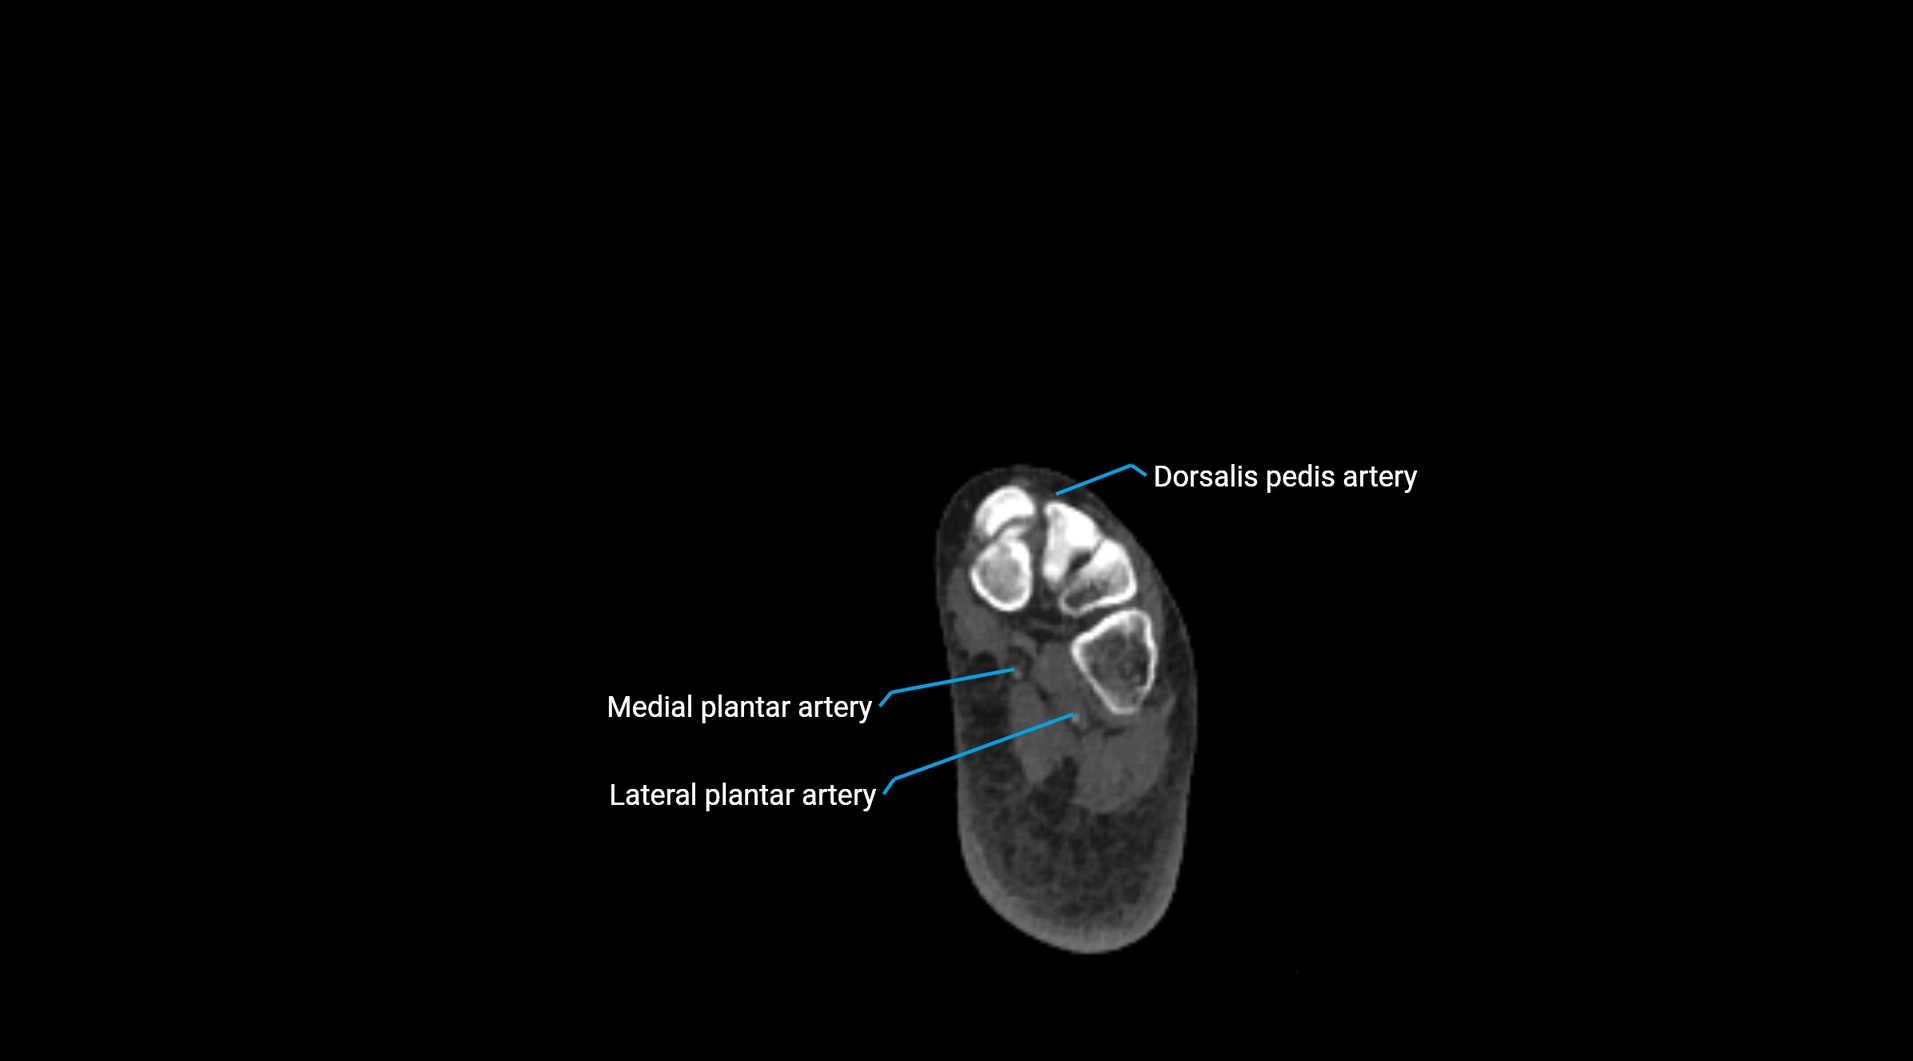

Contrast-enhanced CT (CTA):

• Gold standard for abdominal aortic imaging

• Provides excellent detail of lumen, wall, aneurysm, thrombus, and branch vessels

• Multiplanar and 3D reconstructions help in aneurysm measurement, stent graft planning, and dissection evaluation